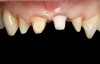

Fig 5. Preoperative photographs showing implant in place of maxillary left central incisor.

Figure 5

Fig 6. Preoperative photographs showing implant in place of maxillary left central incisor.

Figure 6

A 57-year-old woman presented to the dental office with a provisional fixed bridge replacing her maxillary central incisors. The abutment for the bridge was on her maxillary right central incisor, and the pontic was cantilevered off this abutment to replace a missing left central incisor (Figure 5 and Figure 6). The implant had been placed by a periodontist 6 months prior, and the patient was now ready to obtain her definitive implant-supported restoration. The need for the implant was due to a fractured endodontically treated tooth. The patient history revealed that she had been hit in the mouth with a stick as a teenager; her dentist at the time performed endodontic therapy on the left maxillary central incisor, followed by a metal post and core, and placement of a porcelain-fused-to-metal crown on both maxillary central incisors. Two years prior to her current visit, the patient developed pain and tenderness at the apex of the left central incisor, and a radiograph revealed a radiolucent apical lesion. A computed tomography (CT) scan was taken, and an endodontist determined that the tooth was not restorable due to a vertical root fracture. She was referred to a periodontist, who extracted the tooth, placing an osseous graft at the time of extraction for socket preservation, then replaced the extracted tooth with a cantilever pontic. Four months later, an implant was placed and the provisional was cemented back into place. A phone conversation with the periodontist who placed the implant revealed the type of implant used and confirmed that the implant was ready to be loaded and restored.